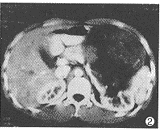

CT检查: 左肾下极见16cm×10cm×16cm巨大囊实性肿块,CT值20.1~48.6HU,肿块边界清 楚,占据左半腹腔(图1),左肾盂轻度扩大。增强后肿块实质部分有轻度强化,CT值62.5H U,可见完整包膜(图2)。右肾无异常,无肿大淋巴结。CT诊断:左肾巨大占位病变,肾母 细胞瘤可能性大。

图1 CT平扫显示腹腔左侧约16cm×10cm×16cm巨大囊实性肿块,CT值20 .1~48.6HU,肿块边界清楚 图2 CT增强扫描示肿块与左肾相连,实质部分有轻度强化,CT值62.5HU ,可见完整包膜。右肾正常